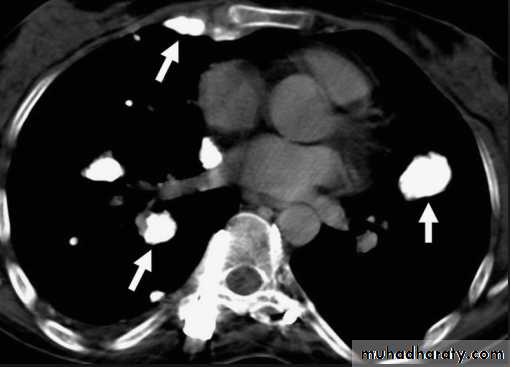

Sarcoid.

Marked lymphadenopathy (dotted lines) is seen in the region of both hila in the right paratracheal region (A).The transverse contrast-enhanced computed tomography scan of the upper chest (B) clearly shows the ascending and descending aorta (Ao) as well as the pulmonary artery (PA) and superior vena cava. The right and left main-stem bronchus area also is seen. Arrows, the extensive lymphadenopathy.